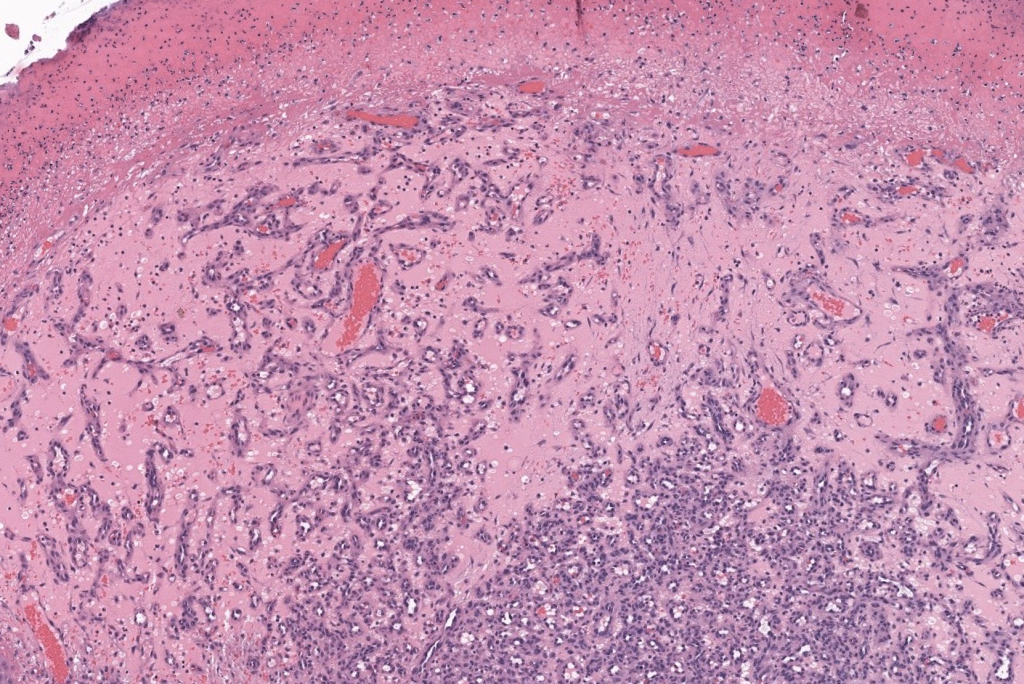

- Tumor vascular benigno adquirido, caracterizado por una proliferación lobular de capilares en piel y mucosas → hoy se prefiere el término hemangioma capilar lobular (HCL); “granuloma piógeno” es un «misnomer» (no hay pus ni granuloma verdadero).Jafarzadeh 2006, Wollina 2017

- Sinónimos frecuentes: granuloma piógeno, granuloma telangiectásico, hemangioma capilar lobular, “tumor del embarazo” / granuloma gravídico (forma gingival en gestantes).Jafarzadeh 2006